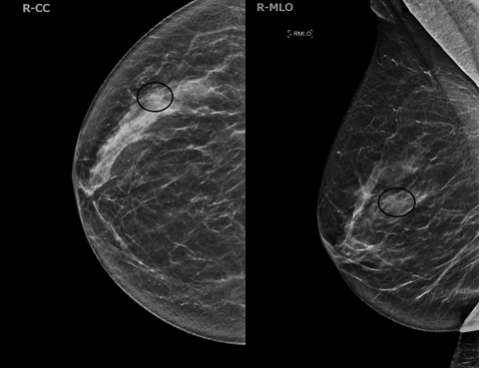

- Mammography/Digital Breast Tomosynthesis (DBT):

ILC cells preserve the architecture of ducts, limiting the detection of mammography. The sensitivity of mammography is 57-81%, with up to 30% of cases not at all visible, while the specificity is 34%1. The most common mammographic presentations are a mass with spiculated or indistinct margins (44%-65%) and architectural distortions (10-34%)1. Some less common findings are asymmetries, focal asymmetries, and shrinking breast appearance over time. DBT produces thinner slices and thus reduces the tissue masking effect of mammography. These two modalities are described together in the literature for ILC detection rates.

Case 1: